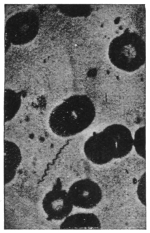

83Section of stomach of Anopheles with malarial oöcysts. (After Grassi)163